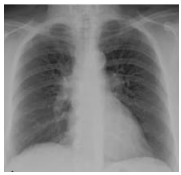

A imagem apresentada abaixo corresponde a

um exame comumente utilizado na avaliação

inicial de doenças torácicas, incluindo

condições pulmonares agudas e crônicas. Com

base nas características visuais da imagem,

assinale a alternativa que indica corretamente o

tipo de exame realizado.

Fonte: ROADDUS, V. Courtney. Murray & Nadel Tratado de Medicina Respiratória.